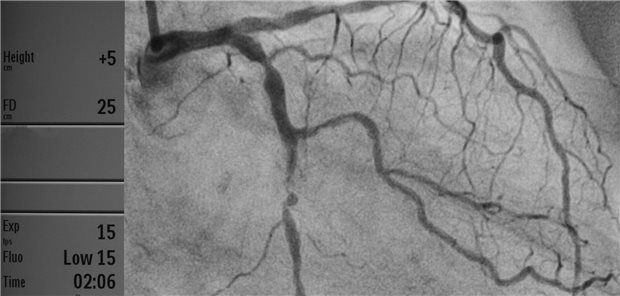

Insgesamt wiesen Patienten mit Diabetes nach der revaskularisierenden Maßnahmen über fünf Jahre hinweg betrachtet ein höheres Sterberisiko auf und waren häufiger von kardiovaskulären Ereignissen betroffen. Dabei zeigten sich aber weder bei Patienten mit noch bei jenen ohne Diabetes signifikante Unterschiede in der Mortalität und im Risiko für frühe Schlaganfälle zwischen PCI- und Bypass-Patienten.

© Pitchy / stock.adobe.com

Stenose der linken Koronarie

Wie sich Diabetes auf den Revaskularisationserfolg auswirkt